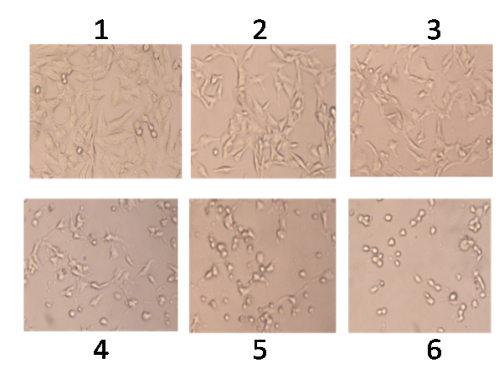

The growth of cancer cells was inhibited in a dose-dependent manner after exposure to the phytochemical (fig. 1, 2), whereas normal human lymphocytes were not affected after exposure (fig. 3). The effect of flavonoid kaempferol on the proliferation of two cancer cell lines (HCT-15 and MDA MB 231) and normal lymphocytes were determined using MTT assay. The IC50 values for kaempferol on HCT-15 and MDA MB 231 were evaluated as 120±3.2 µg/ml and 64±1.2 µg/ml respectively (table 1). When the activity of kaempferol against cancer cells was compared with that against normal lymphocytes it was evident that kaempferol had specific anti-proliferative activity against the two cancer cell lines tested (fig. 4). Further studies were performed based on the IC50 concentrations.

Fig. 2: Effect of phytochemical (kaempferol) on MDA MB 231, cells treated with concentrations. (1) control; (2) 5 µg/ml; (3) 10 µg/ml; (4) 25 µg/ml; (5) 50 µg/ml; (6) 100 µg/ml. Cells were visualized under phase contrast inverted microscope (Magnification X40)